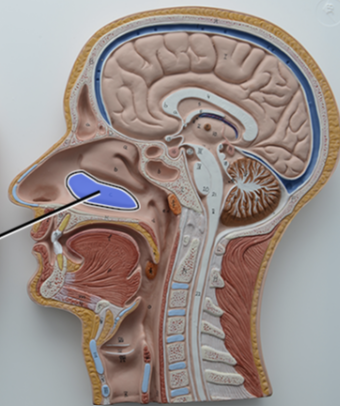

What structure is this?

Diaphragm

What structure is this?

Hard Palate

What structure is this?

Soft Palate

What structure is this?

Uvula

What structure is this?

Nasal cavity

What structure is this?

Superior Nasal Concha

What structure is this?

Middle Nasal Concha

What structure is this?

Inferior Nasal Concha

What structure is this?

The nasopharynx region of the pharynx

What structure is this?

The Oropharynx region of the pharynx

What structure is this?

The Laryngopharynx region of the pharynx

Nasal Septum